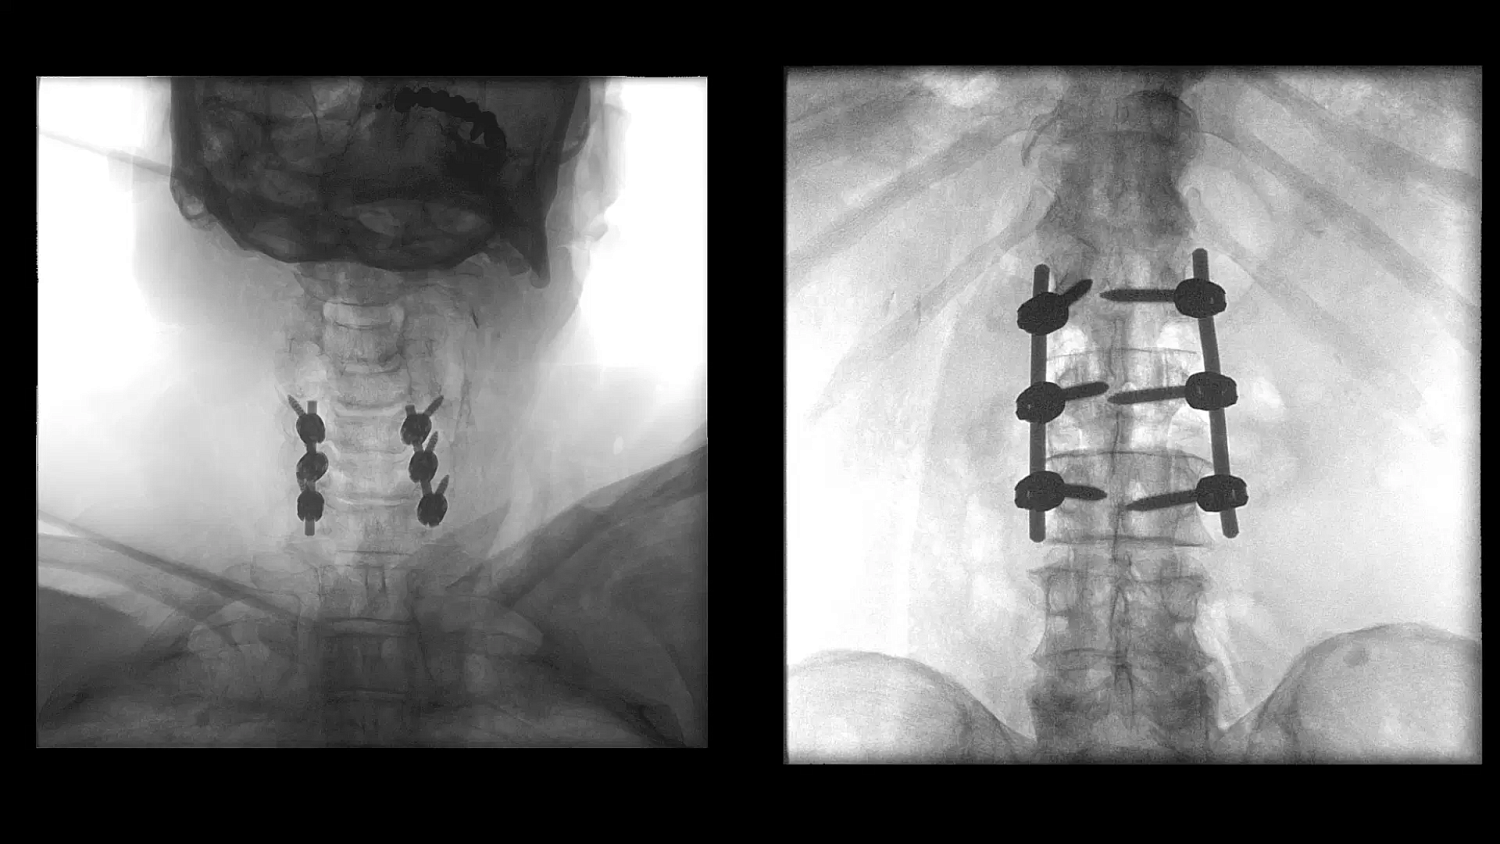

- Улучшенная цепочка визуализации матричного детектора с технологией CMOS: интеллектуальные алгоритмы автоматически регулируют яркость и контрастность, обнаруживают движение, улучшают края и оптимизируют визуализацию металла для улучшения изображения окружающих тканей

Больницы сталкиваются с ростом стоимости медицинского оборудования, поэтому им необходимо оправдать инвестиции. Cios Flow — это многофункциональная система, которую можно использовать в различных областях — ортопедической и травматологической хирургии, хирургии позвоночника, сосудистой хирургии и т. д. — позволяя повысить эффективность использования своих ресурсов.